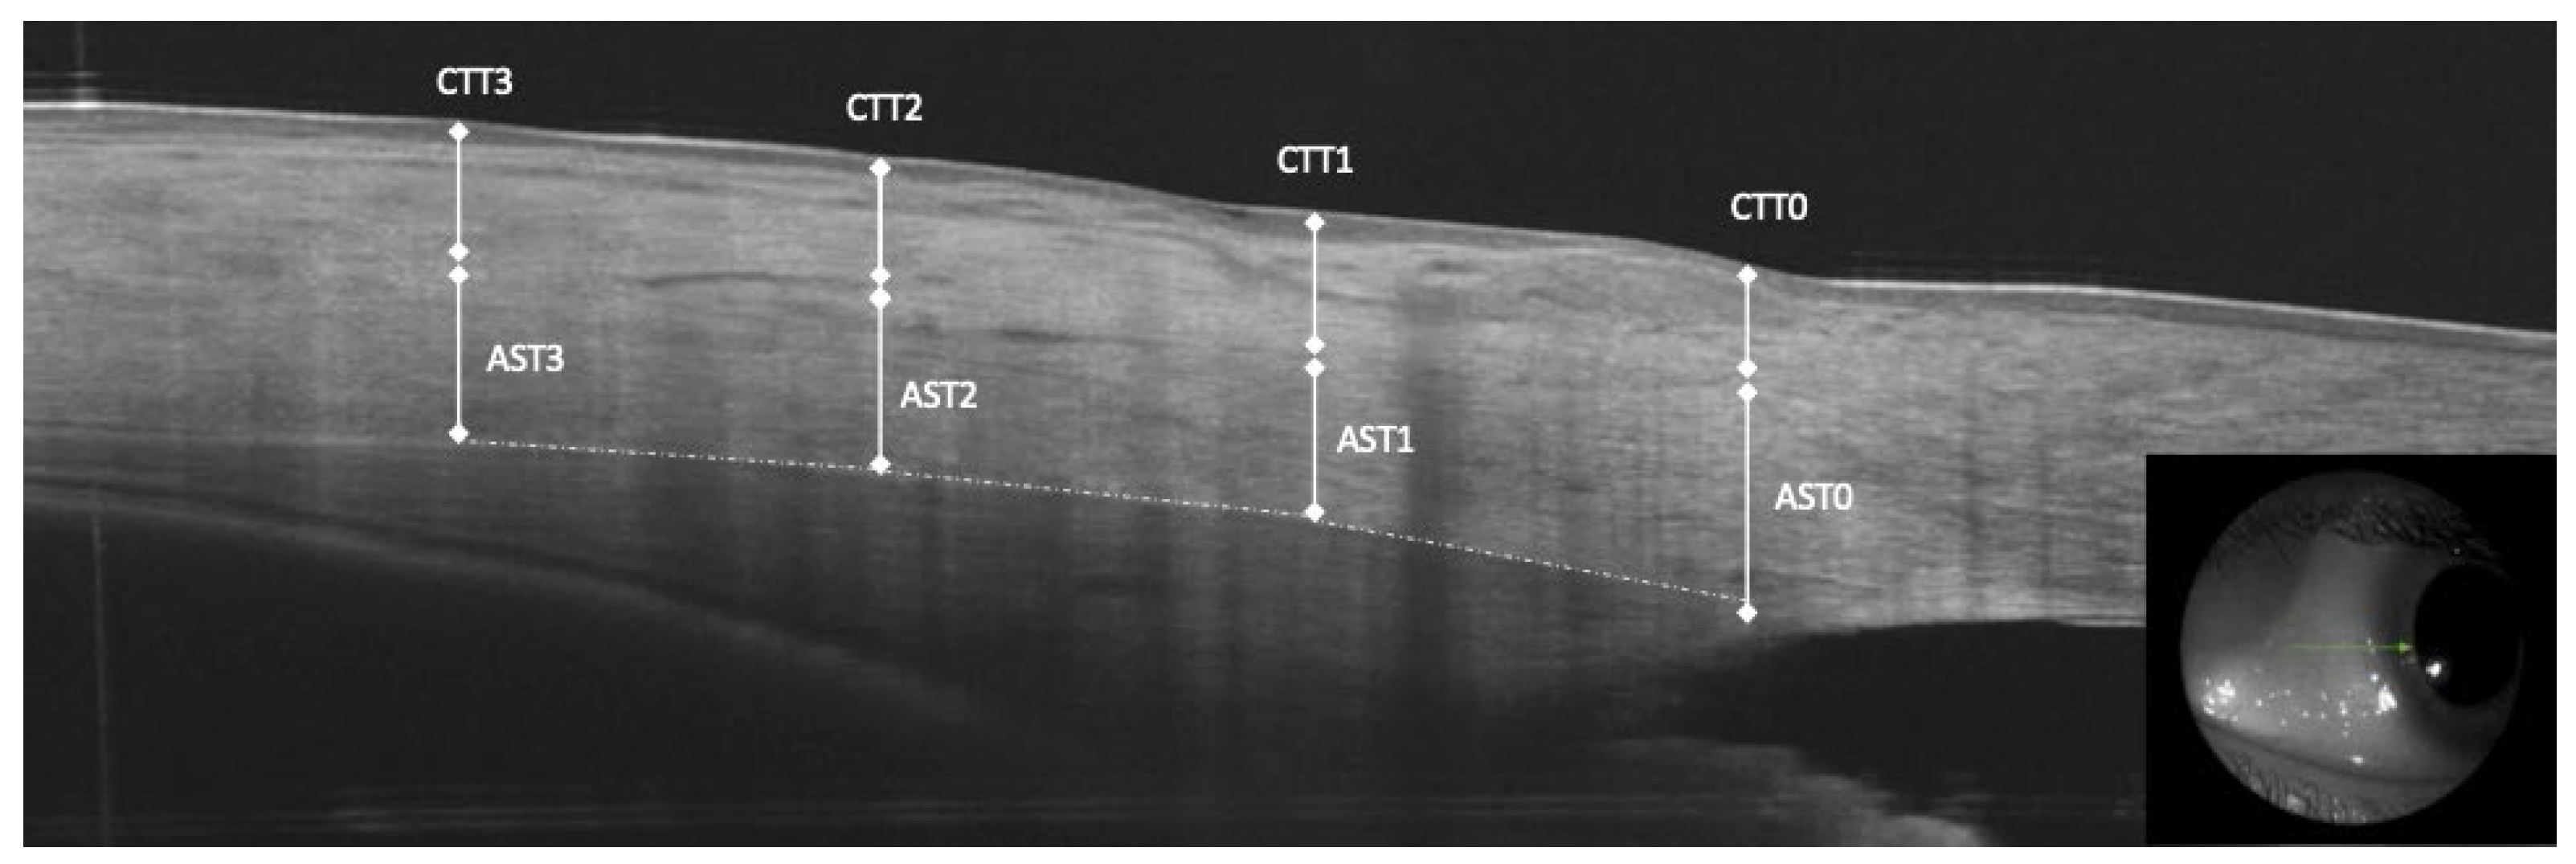

2.3. OCT Measurements